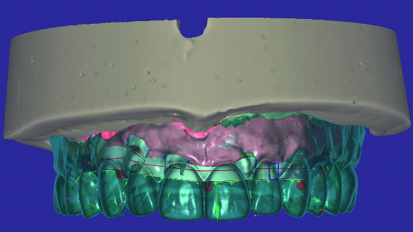

Mastering the implant digital workflow

Whether we like it or not, we are embracing the digital era in our brave new world. Many dental practices are now becoming paper-free—a digital ...